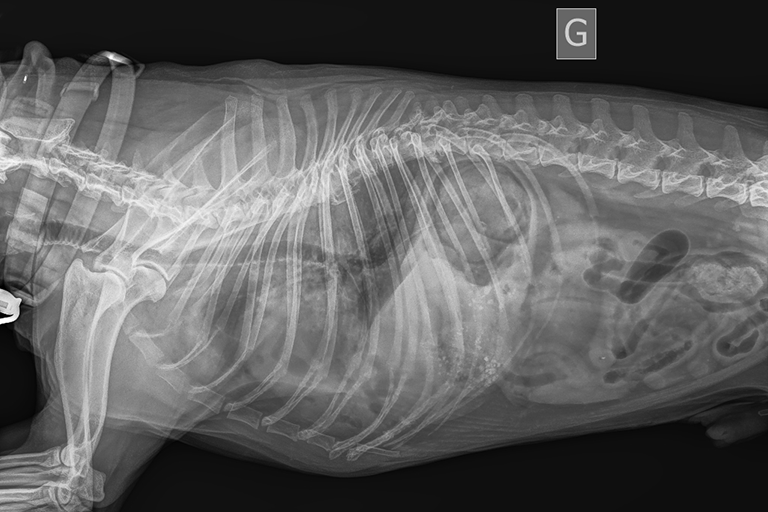

Exploration abdominale

Grâce à la radiographie, le vétérinaire peut visualiser une grande partie des organes abdominaux. Le plus souvent, une échographie d'urgence vient compléter les examens d'imagerie réalisés pour confirmer ou infirmer des lésions.

En urgence, le vétérinaire peut avoir recours à la radiographie abdominale lorsqu'il suspecte une dilatation/torsion de l'estomac, une hernie diaphragmatique ou encore une hémorragie interne.

En pratique, si votre animal présente des symptômes digestifs (diarrhée ou vomissements), il est éligible à une radiographie de l'abdomen.

Suspicion d'occlusion

Les cas d'occlusions intestinales sont fréquents chez les chiens et chats. Pour mettre en évidence cette pathologie, la radiographie d'urgence est indiquée. Plus particulièrement, l'examen recommandé est un transit baryté, qui consiste en une succession de 5 à 7 radiographies prises à intervalles réguliers après ingestion d'un produit de contraste.

Le transit baryté permet de visualiser une interruption du transit intestinal lié à une occlusion, un iléus paralytique, un iléus spastique ou une intusucception. Toutes ces lésions nécessitent une chirurgie d'urgence, réalisée au Cabinet Vétérinaire de Garde de Toulouse.